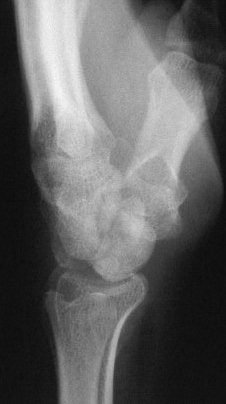

Carpal tunnel developed and progressively worsened, probably related to the palmar prominence of the lunate. The patient underwent carpal

tunnel release and midcarpal fusion and returned to heavy manual work.